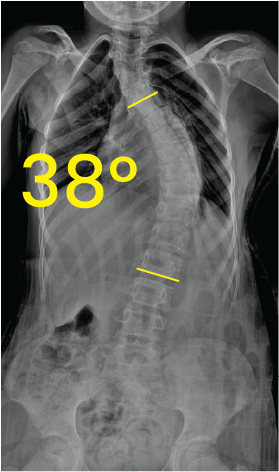

X-ray image of a human torso showing a 48-degree spinal curvature indicative of scoliosis.X-ray image of a spine showing scoliosis with a 38-degree curvature marked between two yellow lines.

Göğüs röntgeninde omurgada 38 derece skolyoz açısını gösteren sarı çizgiler ve 38° rakamı.Göğüs ve lomber omurgada 29 derece skolyoz eğrisi gösteren röntgen görüntüsü.